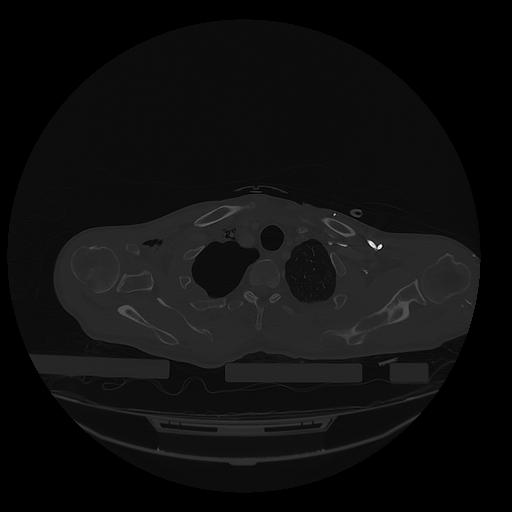

31 PULMON,CE,Vol,1.0,PULMON,,